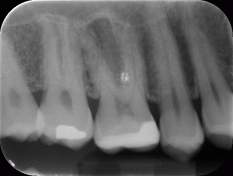

Il caso è di un maschio 46enne con l’elemento 16 (primo molare superiore di destra) presentante otturazione di amalgama infiltrata. Dopo aver effettuato i 4-5 tests clinici valutativi, si è eseguita l’anestesia locale e iniziata la rimozione della stessa e della dentina cariata.

Dopo aver scoperto parte della camera pulpare (la zona in cui è presente il “nervo”) si è proceduto ad eseguire l’incappucciamento diretto con BIODENTINE (septodont), un materiale appartenente alla classe dei cementi portland con una elevata biocompatibilità e caratteristiche meccaniche molto simili a quelle della dentina naturale.

Dopo quasi due mesi si è proceduto alla preparazione della cavità e alla realizzazione dell’impronta per la realizzazione di un intarsio in composito rinforzato.

Si può notare la risposta positiva della polpa e la soddisfazione del paziente nell’avere, a distanza di più di un anno, il suo dente ancora vitale.